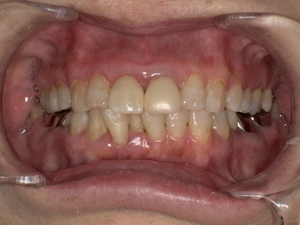

After(治療後)

ジルコニアセラミッククラウンを装着することで、自然な見た目を回復し、しっかり噛める状態に改善しました。

患者様にも「自然な歯のようで違和感がない」とご満足いただきました。